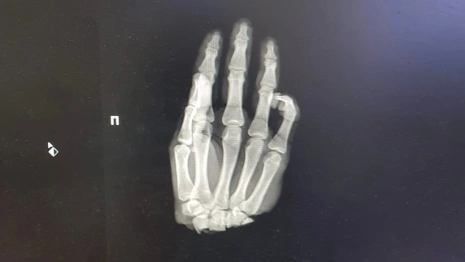

Врачи нижегородской клиники ПИМУ спасли отрубленную кисть руки у 16-летнего подростка из Коврова. Об этом сообщила пресс-служба вуза в субботу, 4 марта.

Парня доставили в больницу 1 марта. Он отрубил себе кисть, когда колол дрова.

Врачи провели операцию по реимплантации конечности. Сейчас состояние пациента стабильное. Медики восстановили кровоснабжение кисти.

Пациенту понадобится еще несколько операций, чтобы восстановить функционирование конечности.